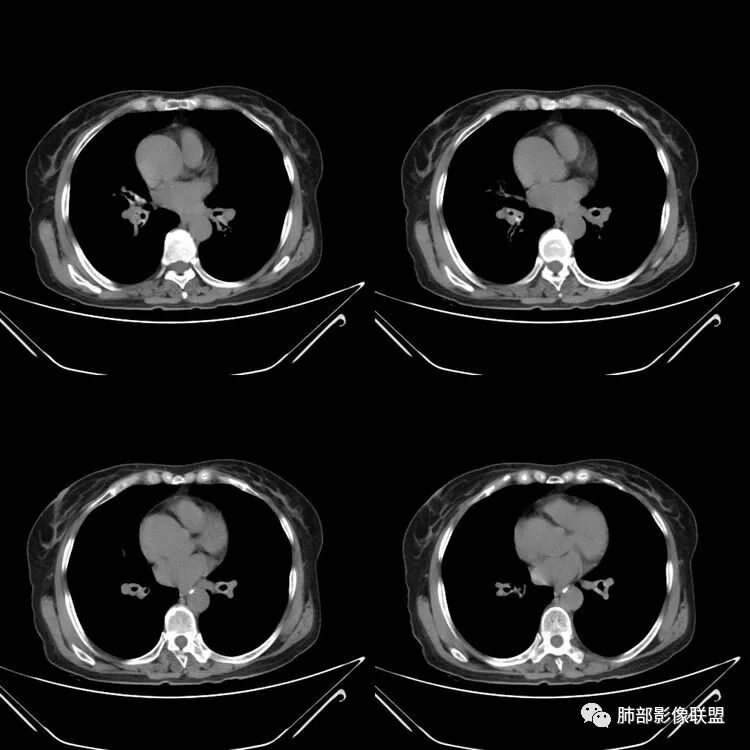

患者,女,64岁,反复咳嗽、咳痰、胸闷10年,加重2周。气管支气管及两肺下叶 支气管弥漫性的环状增厚,管腔扩张,管腔感觉比较松弛。第一感觉,气管支气管淀粉样变。鉴别诊断,1、支气管内膜结核,肺内散在一些支气管的播散病灶,粟粒结节为主,形态比较单一。2、复发性的多软骨炎,就得了解一下其他部位,有没有多个部位的软骨炎。这个病人右侧胸廓缩小,升主动脉明显的扩张,其横径明显的超过了降主动脉。

南边:肺部有肺气肿支气管腔狭窄淀粉样变性?复发性多软骨炎?血管炎?慢支?结核?曲霉菌?南边:一般还是淀粉样变性与复发性多软骨炎鉴别其次就是支气管骨化症,但是骨化下朝上,且壁结节状钙化明显,本例不太支持。至于结核、曲霉菌?1.结核,一般不会这么广泛,支气管壁狭窄后扩张2.曲霉菌可以这么广泛,但是支气管壁管腔扩张,而且附近脂肪间隙有炎性反应,不太支持;3.血管炎,一般合并肺内有病灶,但是声带受累,放待排;4.软骨炎一般全身受累,例如耳廓等;而且膜部不受累,不太支持;倾向于淀粉样变性;淀粉分很多型,气管支气管是最常见的。尘缘:影像上生理性钙化与支气管骨化无法区别,镜检也不好鉴别,需要依赖活检,看粘膜中是否合并炎性改变(淋巴细胞,组织细胞等炎性细胞侵润)来鉴别Coke with ice:经常看到的这种是老年性肺改变,又称年龄相关肺改变。气管和支气管弥漫性软骨钙化,常见老年女性。尘缘:支气管骨化症很罕见的,所以绝大多数还是生理性钙化。对于老年人,无临床症状的钙化,还是基本上都是生理性钙化,无临床意义。大雄:如果管壁钙化伴明显增厚 影像还是提示一下建议支气管镜稳妥些